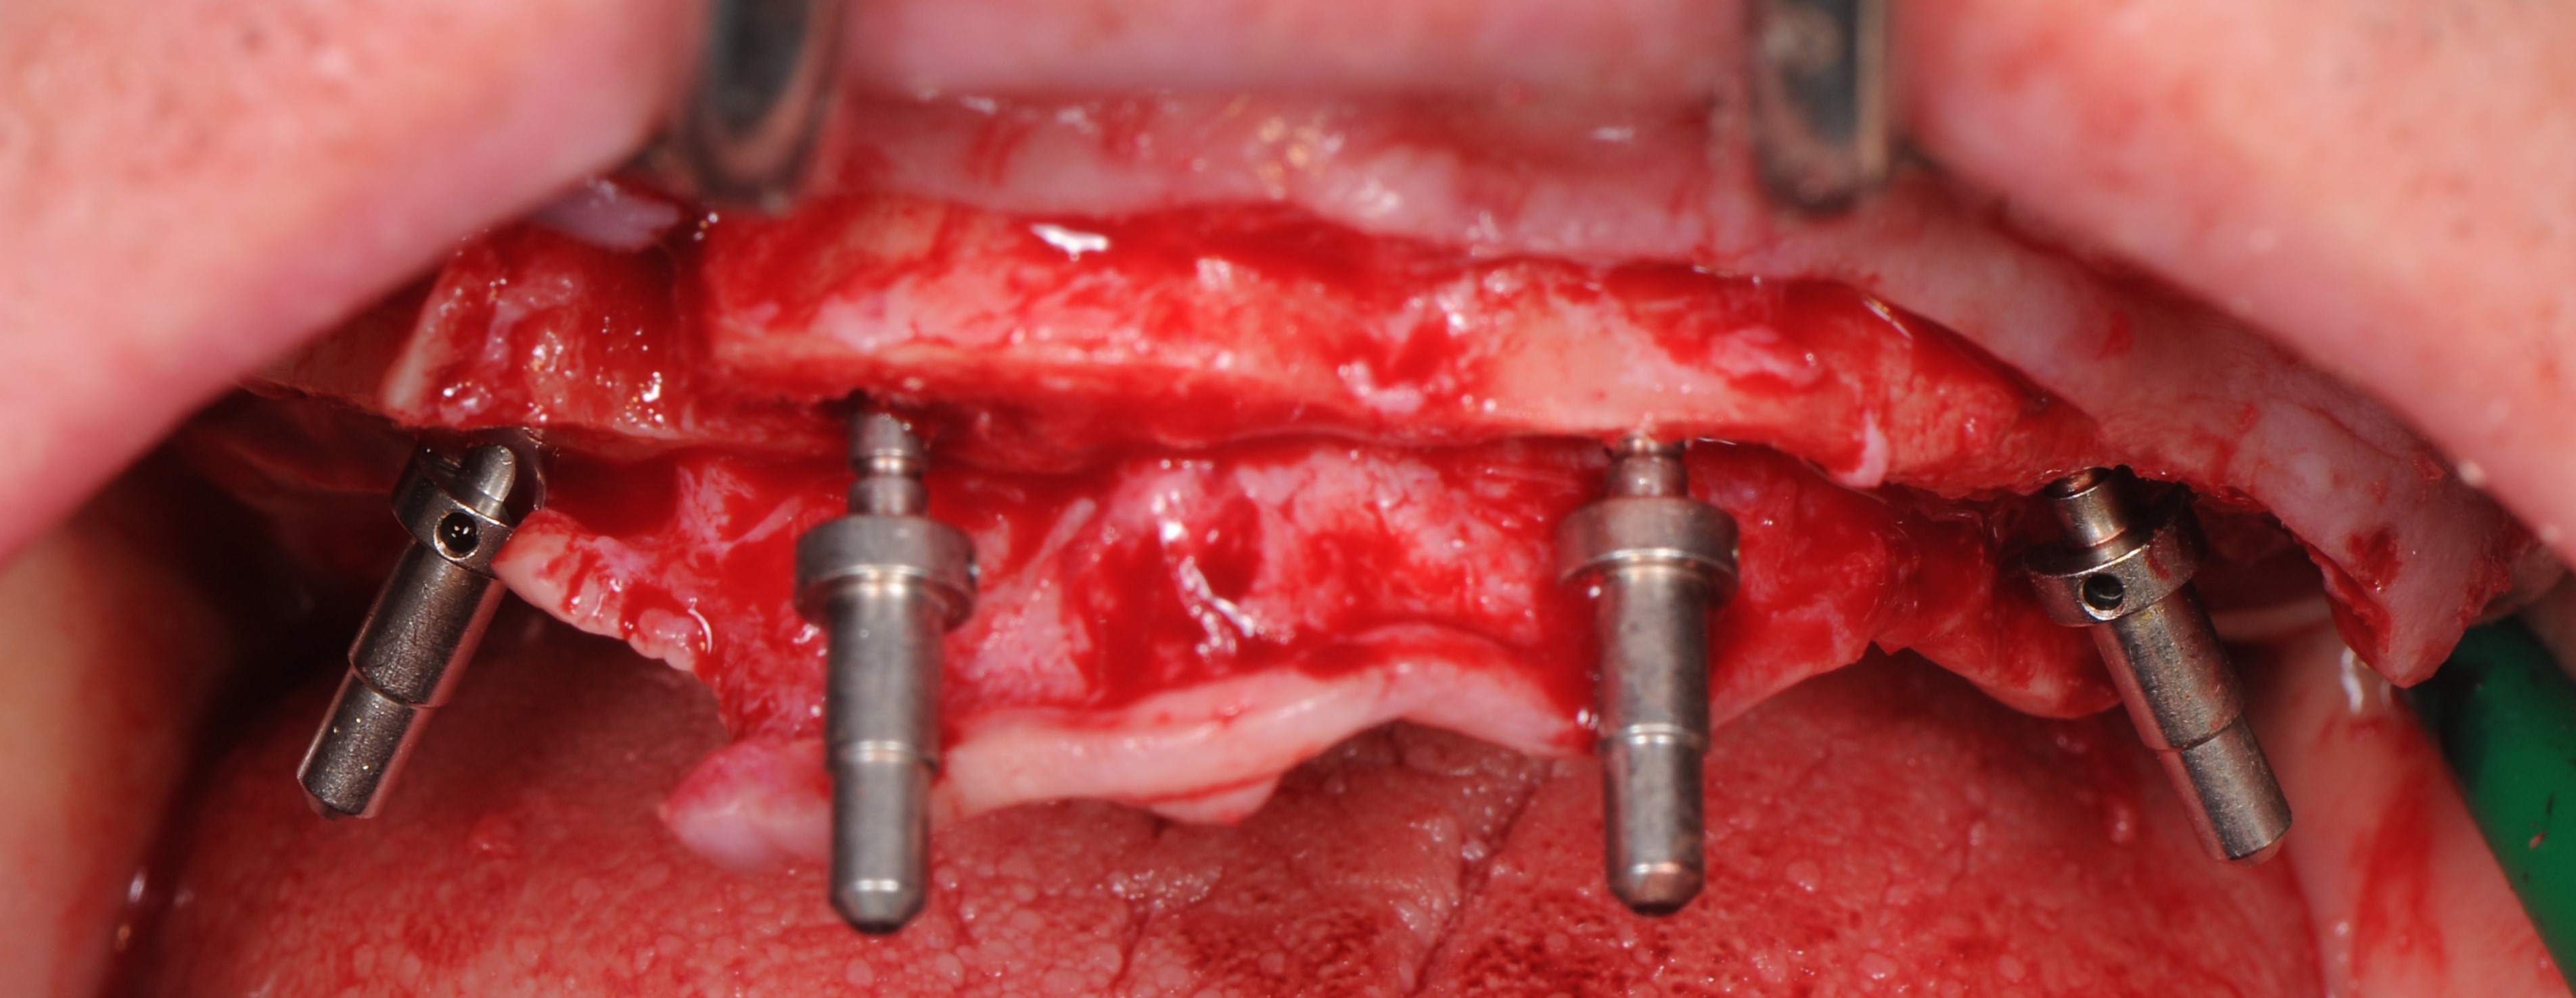

По протоколу неполного препарирования было выполнено формирование ложа для дентальных имплантатов «Nobel Parallel Conical Connection» с последующей их установкой по методике «All –on – 4». Дистальные имплантанты установлены под углом 30°, имплантаты во фронтальной зоне – вертикально(рис. 14-19). Торк (крутящий момент) всех установленных имплантатов составил более 35 N/см2 что, позволило нам одномоментно нагрузить все установленные имплантаты с установкой временного условно-съёмного протеза из акриловой пластмассы с титановым каркасом.

На имплантаты были установлены абатменты для винтовой фиксации «Multi – unit»: в боковых участках угловые 30О абатменты , во фронтальных участках – прямые абатменты (рис. 20,21)